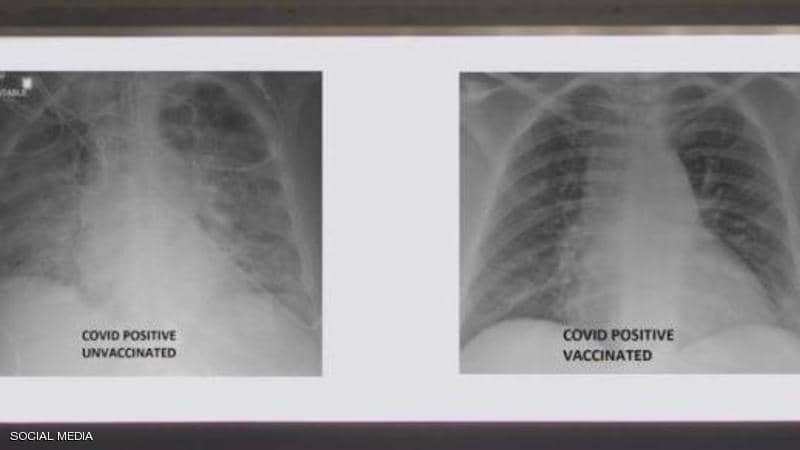

بالصورة: الفرق بين رئتي شخص مطعم ضد كورونا وآخر غير محصن

نشر الطبيب العربي في الولايات المتحدة، غسان كمال، صورة تظهر الفرق بين رئتي شخص جرى تطعيمه ضد فيروس كورونا ورئتي شخص آخر لم يتلق التطعيم، مشيرا إلى أن الاثنين أصيبا بفيروس كورونا.

وأظهرت صور الأشعة السينية، أن رئتي الشخص غير الملقح، المصاب بفيروس كورونا كانت بيضاء بصورة شبه كاملة وتعرف بـ”عتامة الرئة”، مما يعني أنها كانت غارقة في الفيروس، في حين أبرز صور رئتي الشخص ببيضاء أقل.

وتعني صورة الأول أيضا نقصا في دخول الهواء إلى رئتيه، فيما تعني لدى الثاني أن الهواء يتدفق بسهولة علاوة على أن رئتيه خاليتين من الوباء.